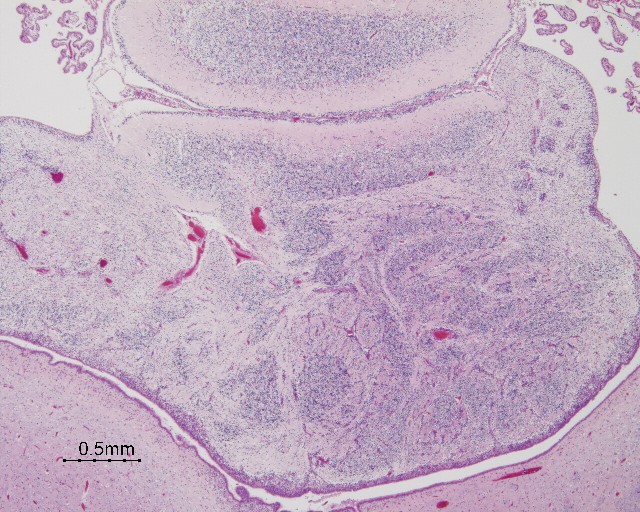

Cerebellar heterotopia of infancy

HSC A04-220

- Four distinct histological types:

1. compact groups of mature neurons

2. immature granular cell collections (focal and perivascular)

3. poorly organized mixed cell rests containing mature neurons and immature neuroepithelial cells ("heterotaxia" of Brun)

4. mixed cell rests with normal relationship of the cerbellar cortex represented ("heterotopia" of Brun)

- granular cell collections can collect around vessels, perhaps an extension of the external granular layer along blood vessels

- mixed cell rests occur most frequently

near midline, lateral projections of nodulus of the vermis, roof nuclei, flocculo-nodular lobe

- heterotopic nodules often contain mature neurons surrounded by astrocytes